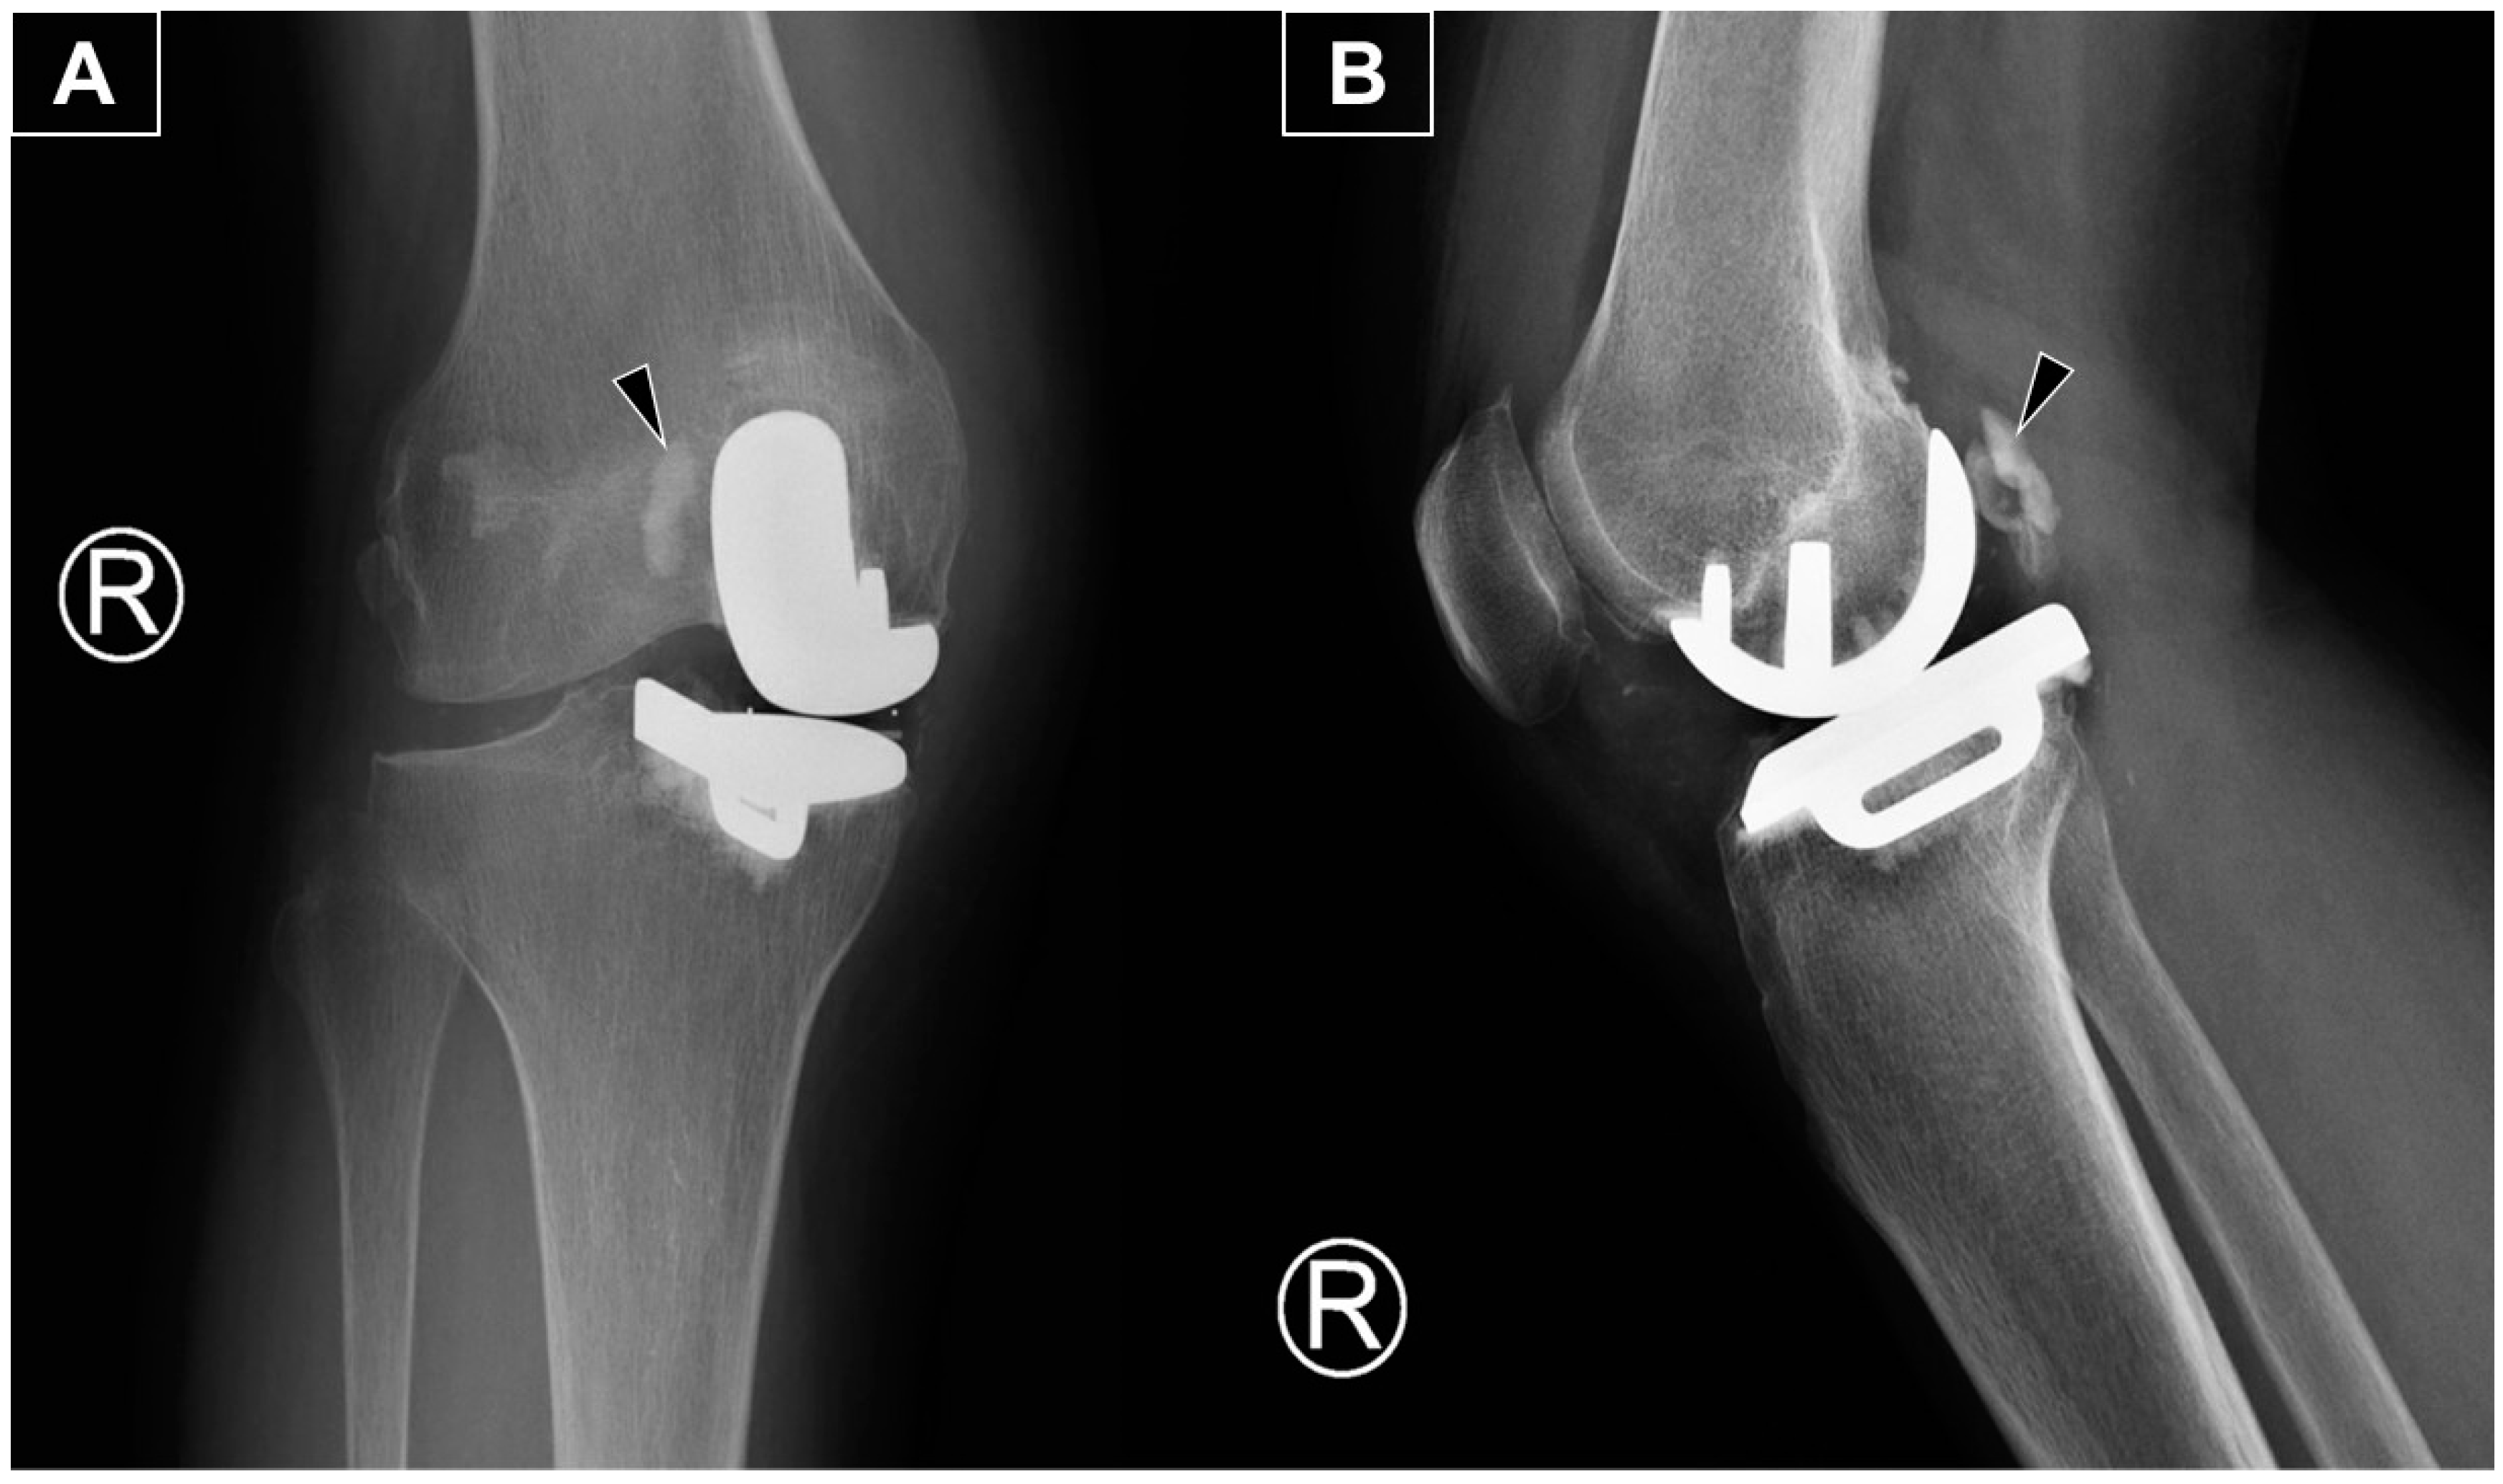

Figure 1. The anteroposterior (A) and lateral (B) radiographs reveal the main portion of the extruded cement (arrowhead) positioned posterolateral to the medial femoral metallic component. The radiograph is from a 66-year-old woman with isolated medial compartment osteoarthritis of the right knee who experienced mechanical knee pain, with a visual analog scale (VAS) score of 7/10. Her symptoms had limited her walking to 30 min with the assistance of a walking stick. She could ascend only one flight of stairs (using a stick and rail support) and was unable to squat due to knee pain and stiffness. After exhausting all non-operative treatments without significant improvement, she underwent a medial uni-compartmental knee replacement. She first presented to our clinic three months postoperatively with persistent knee swelling and posterior knee pain during deep flexion. She was afebrile and ambulated with a walking stick, though with some difficulty. Examination revealed moderate knee swelling with mild warmth and tenderness but no erythema. The surgical wound was well-healed. Active knee extension was complete, and flexion reached 100 degrees actively and 120 degrees passively, with posterior knee tenderness at the end range of flexion. Ligamentous stability was intact, and no posterior swelling or skin changes were observed. There was no calf swelling or other leg symptoms, and the neurovascular examination was normal. Radiographs showed an opacity posterior to the metallic femoral component, consistent with extruded cement from the fixation.

Diagnostics 15 00112 g001